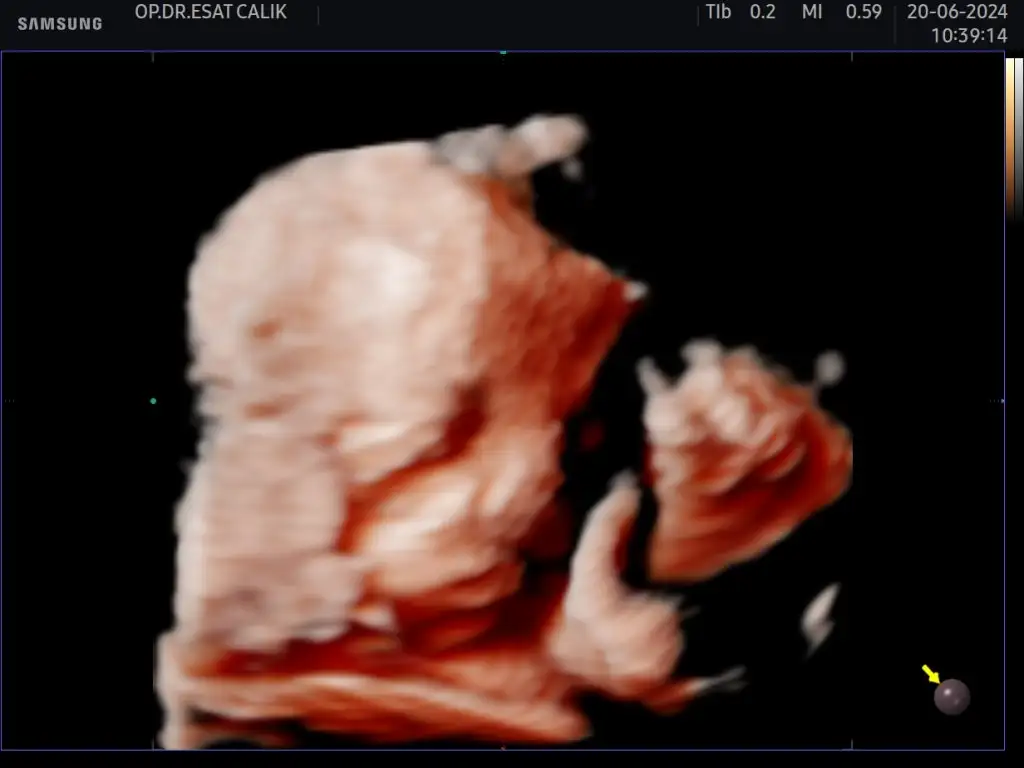

MaşAllah minnoşaKızlar bugün özel muayenehanesi olan doktoruma gittim 31+3 üz 41 cm 1776 gr çıktık mantar için fitil verdi herşey yolunda çok şükür oğluma merhaba deyin plasentam önde olduğu için ancak bu kadar net çıkabiliyo fotolar maalesefEki Görüntüle 3442290

Benimkide detaylıda bile zor gösterdi en son muayenede eliyle yüzünü kapamıştı şimdi de tam net değil ama idare edicezMaşAllah minnoşabenimki 3 aydır göstermiyor yüzünü ufaktan da olsa en son detaylıda gördüm o kadar